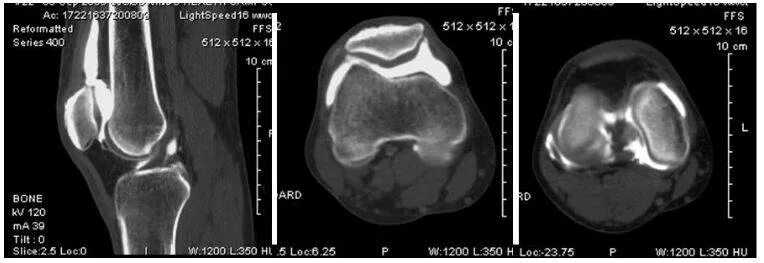

Кт суставов что показывает